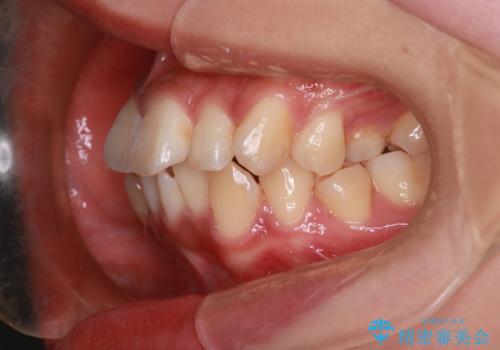

- 前歯の突出が強く、口元が前に出ている印象を改善するため、上下左右の第一小臼歯(4番)を抜歯する矯正治療を計画しました。抜歯により得られたスペースを利用して、前歯を後方へと移動させて整列します。治療には目立ちにくい透明な審美ブラケットとワイヤーを使用し、毎月1回の調整を行いながら徐々に歯を動かし、約2年で口元全体を整える計画としました。

前歯が前に出ているため口元が突出し、唇が閉じにくいなどの悩みを抱えておられました。治療にあたり上下左右の第一小臼歯を抜歯し、十分なスペースを作ることで前歯を効果的に後方へ移動させました。装置には透明で目立ちにくい審美ブラケットを採用し、治療中の審美的ストレスを軽減しました。定期的な調整を通じて無理なく確実に歯列を整え、前歯の突出感を解消。治療後は口元の印象が自然で美しく改善され、患者様には非常にご満足いただけました。